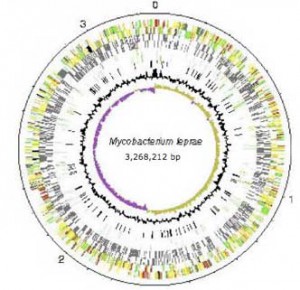

M. leprae can now be conceptualised as a series of genes that can be grouped and described, often by analogy with those identified in another genome, such as M tuberculosis. Technologies other than the microscope are available to view it. Instead of a sample of tissue in serum under a microscope, it now also exists as a genome database that can be explored via MycoBrowser, a genome browser located on the web at http://mycobrowser.epfl.ch/leprosy.html. A search of the genome can be conducted by gene name, region in the genome, gene function, by DNA or protein patterns, by a search of the DNA sequence or protein sequence. Results are presented as a list or a drawing, and the DNA or protein sequence of a single gene can be viewed or downloaded (Jones, 2001, pp. 470-7). The whole sequence of the chromosome is available. Its density, length, number of genes, pseudogenes, and other respective genetic components are enumerated.

Firstly, it is possible to describe something of the evolutionary changes that have taken place. M. leprae has undergone a loss of genes and a subsequent loss of ability to respond to different environments. It is described as a decaying genome: one that has undergone considerable downsizing during its evolution. It has a trajectory and an ancestry – a former self that was more complex. Less than half of the genome contains functional genes. Its “immediate ancestor may have already undergone reductive evolution and … a single clone then expanded and … disseminated globally” (Eiglmeier et al., 2001a, p. 390). Adaptation has been selective and self-interested. Chromosomal rearrangements, gene deletions and duplications have had a profound effect on the biology of M. leprae and in turn on leprosy itself (Cole et al, 2001, p. 459). Yet this decay is evidence of a reduction in redundant functions so that the major repair pathways are still intact (Dawes et al., 2001, p. 411).

Mapping makes it possible to answer some questions. M. leprae strains from different origins exhibit no obvious, important genome diversity. The genome still retains its full complement of heat shock proteins, explaining why, given its optimal growth temperature is 32°C, it multiplies in the extremities of the body. It is possible to determine the uniqueness of the metabolic pathways of the genome, as well as compare them to that of M. tuberculosis indicating that the survival of M. leprae is dependent on a specialised niche. It has extremely reduced genes for dealing with respiration and an oxygen-rich environment, and hence exists successfully in an intracellular environment, which has relatively constant conditions. The pathogenicity of the mycobacterium depends on its ability to survive in the macrophage or in the Schwann cell. As such it is characterised as “extremely specialised” and it is “irreversibly committed … to a lifestyle characterised by slow growth and necessarily slow central metabolism”. The basis for resistance to dapsone and rifampicin is able to be understood. In addition, the susceptibility of M. leprae to other drugs can be determined. *3